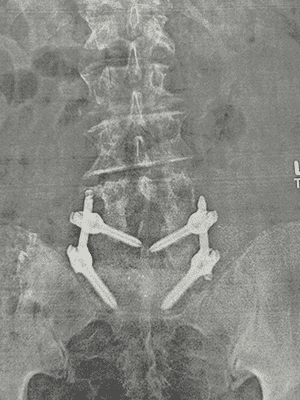

PLIF is aimed at stopping the motion between two spinal vertebrae causing pain. It is typically performed around the L4-L5 or L5-S1 area at the lower base of the spine. A bone graft is inserted between two vertebrae, and custom-made screws, rods and spacers, or cages, may be used to stabilize the spine and allow the vertebrae to heal and fuse together.